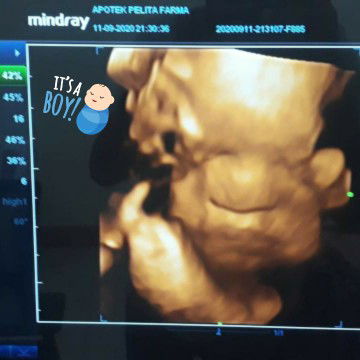

Cara perhitungan usia kandungan??